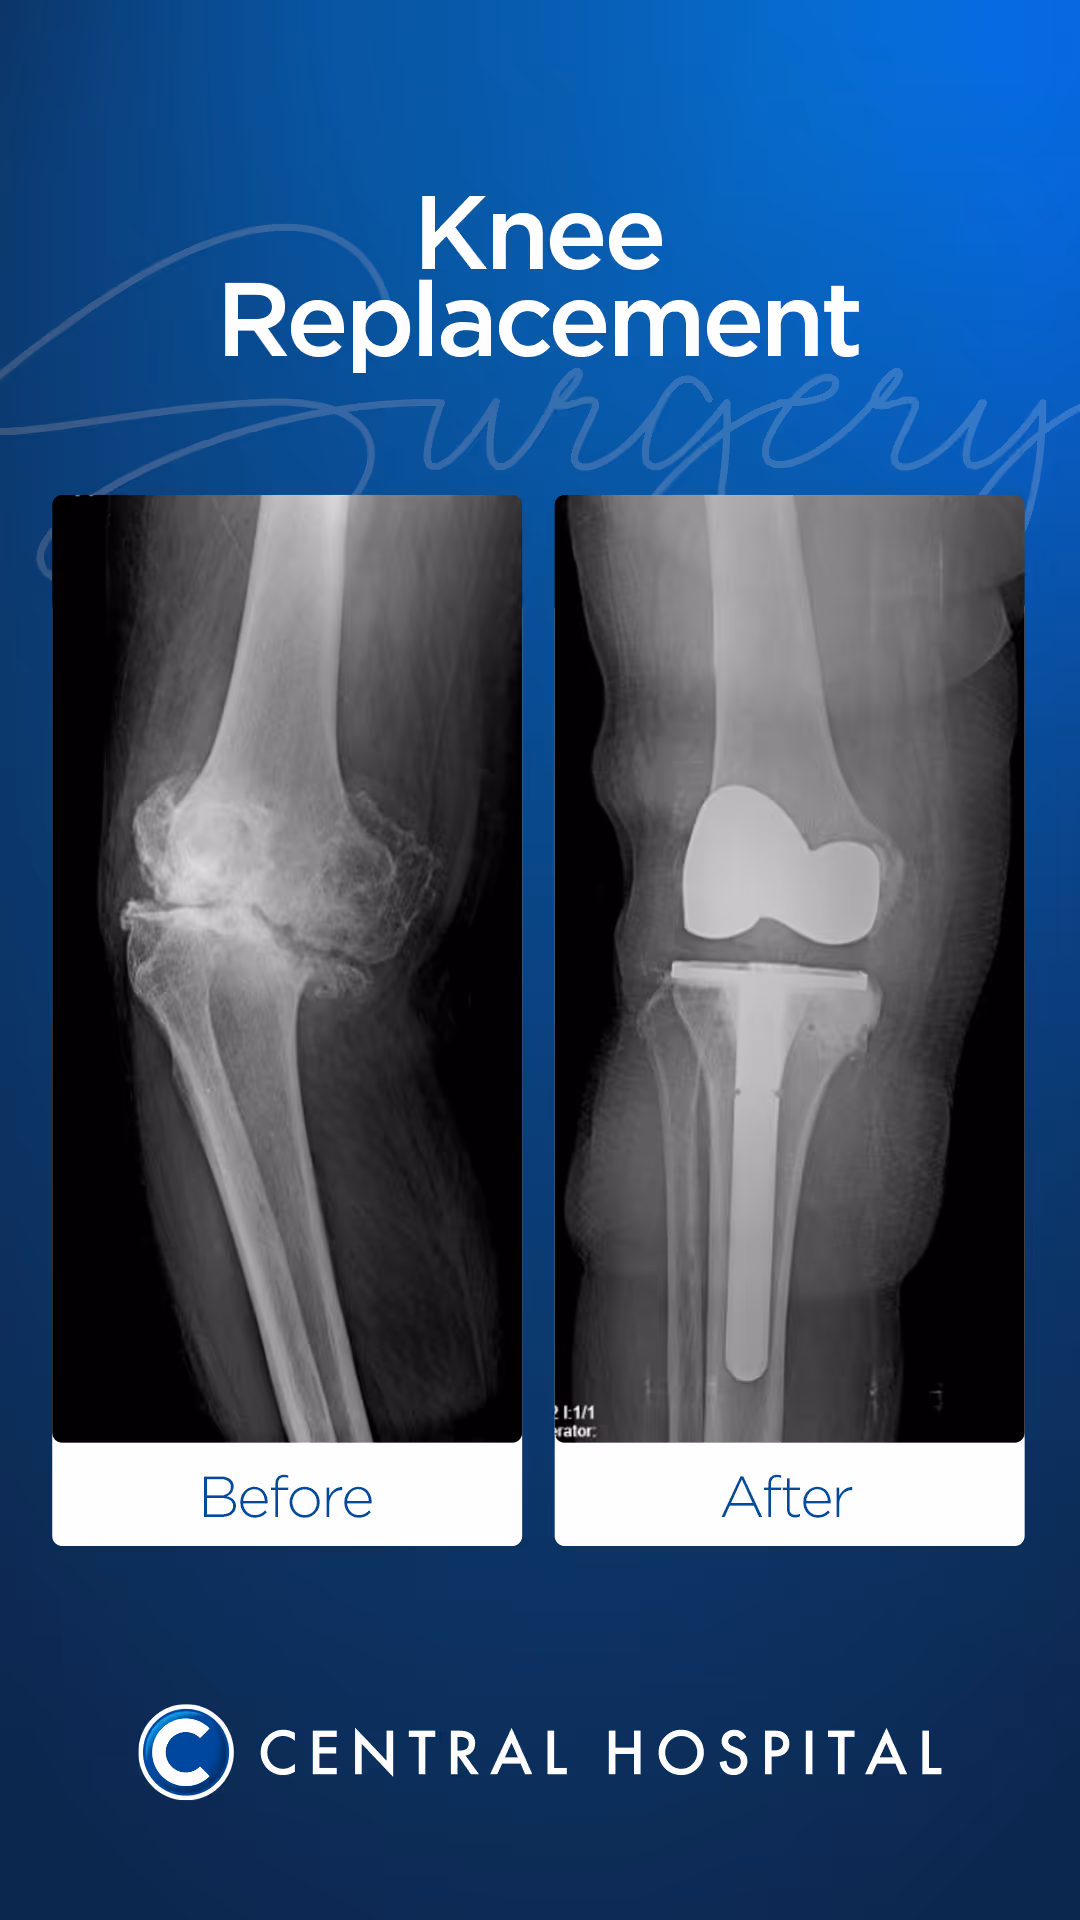

Diz protezi, diz ekleminde ciddi hasar, ağrı veya hareket kısıtlılığı olduğunda uygulanan cerrahi bir tedavi yöntemidir. Genellikle osteoartrit (kireçlenme), romatoid artrit veya travma sonrası gelişen eklem bozukluklarında diz protezi ile eklem fonksiyonları yeniden kazandırılır.

Diz Protezi Ameliyatı

Ameliyat sırasında aşınmış ve hasar görmüş eklem yüzeyleri titizlikle temizlenir ve yerini metal veya özel plastik alaşımlardan yapılan yapay bir ekleme (protez) bırakır. Bu cerrahi planlama; hastanın yaşına, aktivite düzeyine ve kemik yapısına göre kişiye özel olarak yapılır.